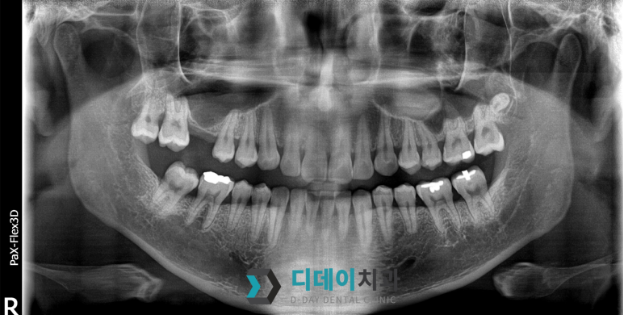

그래서 3D CT 촬영이 필수입니다.

뼈의 두께, 신경의 위치, 잇몸 상태까지

정밀하게 파악할 수 있거든요.